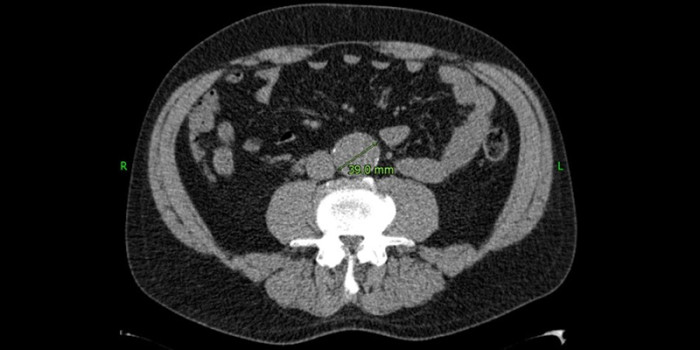

Een snelgroeiend aneurysma van de buikaorta

Soms wordt op een echo of CT van de buik een aneurysma aortae abdominalis (AAA) ontdekt. Vaak gebeurt dat in een ziekenhuis. De radioloog vermeldt die toevalsbevinding meestal wel in de brief aan de huisarts, maar als het AAA ‘klein’ is, wordt meestal niet vermeld dat follow-up geïndiceerd is. Die controle kan echter van levensbelang zijn.